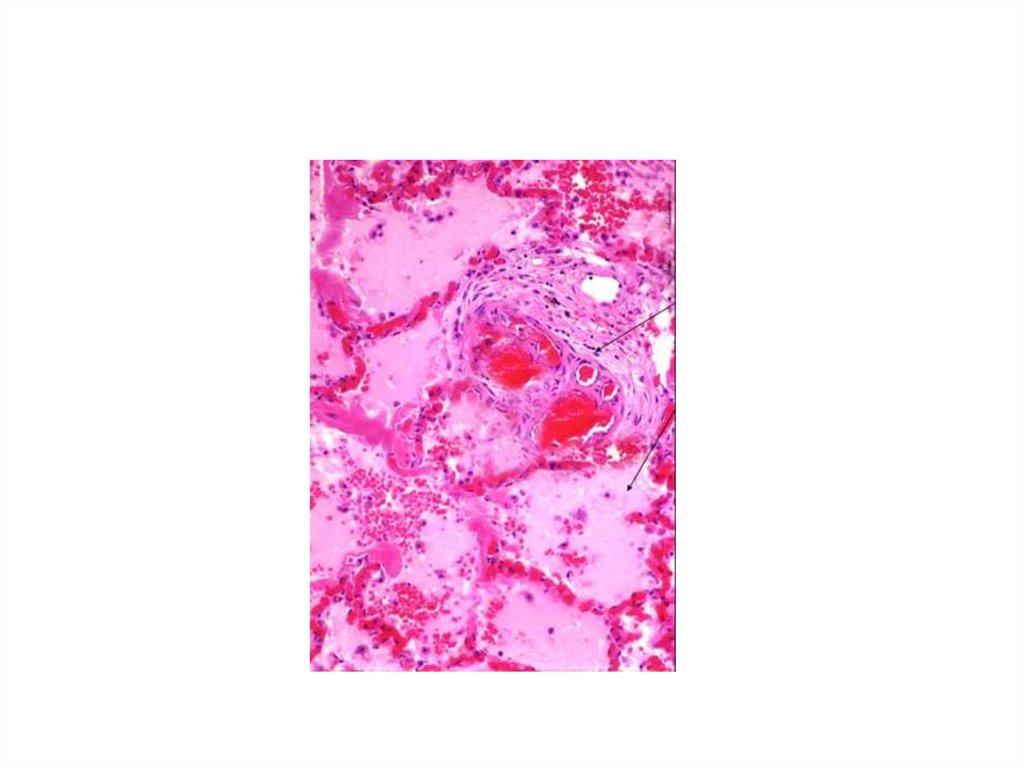

• 3.«Шоковое лёгкое» - в лёгких развиваются

участки ателектазов, серозногеморрагического отёка, с выпотом

фибрина в просвет альвеолярной

мембраны, стаз крови и тромбы в

капиллярах, что вызывает развития острой

дыхательной недостаточности и острого

ресспираторного дистресс-синдрома

взрослых (ОРДСвзрослых).